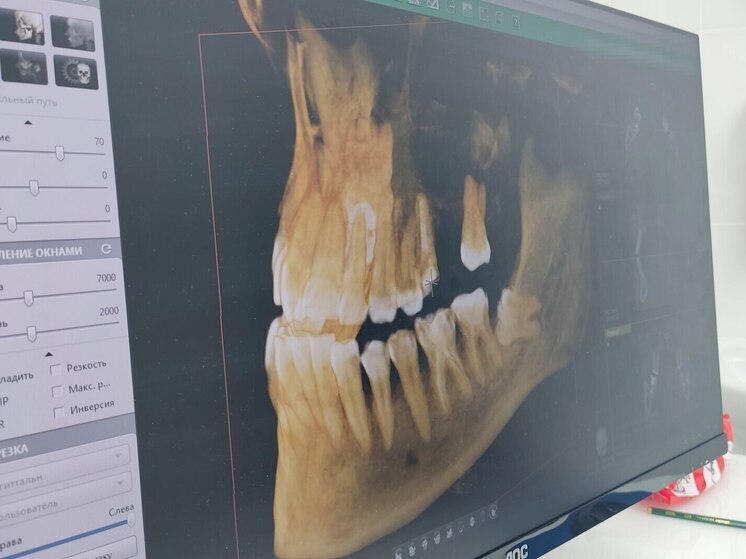

Специалист порекомендовала всем детям и подросткам носить защитные шлемы и по возможности капы для зубов. Фото: Архив МК в Великом Новгороде

На смену летнему сезону травм, когда дети и подростки падали с велосипедов и самокатов, пришёл зимний сезон. В зоне опасности — лыжи, коньки, сноуборды, ватрушки и так далее. О способах безопасного катания, рассказала в интервью «МК в Великом Новгороде» руководитель детского отделения стоматологической клиники Татьяна Петрова.

Специалист рассказала, что самым «богатым» на травмы ежегодно становится январь. Она порекомендовала детям и подросткам надевать защитные шлемы и по возможности капы для зубов, отметив, что падение может оставить человека без зуба.